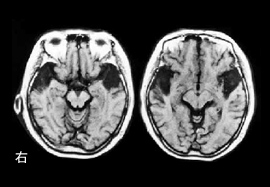

図1.和音認知の障害を来した失音楽症例の脳MRI ※1

筆者による研究の例をあげましょう。図1は両側側頭葉の前部に脳梗塞を生じた結果、失音楽症を来した症例の脳MRI画像です。

患者は無症状で退院しましたが、自宅に帰るとなじみの音楽が分からなくなっていることに気付きました。何度も聞いていたレコードを聞いても何の曲か分からず、ケースを見て初めて慣れ親しんだ曲であることを知りました。

音楽能力の検査を評価したところ、なじみのメロディーが分からなくなっている他に、和音の響きも分からなくなっていました。